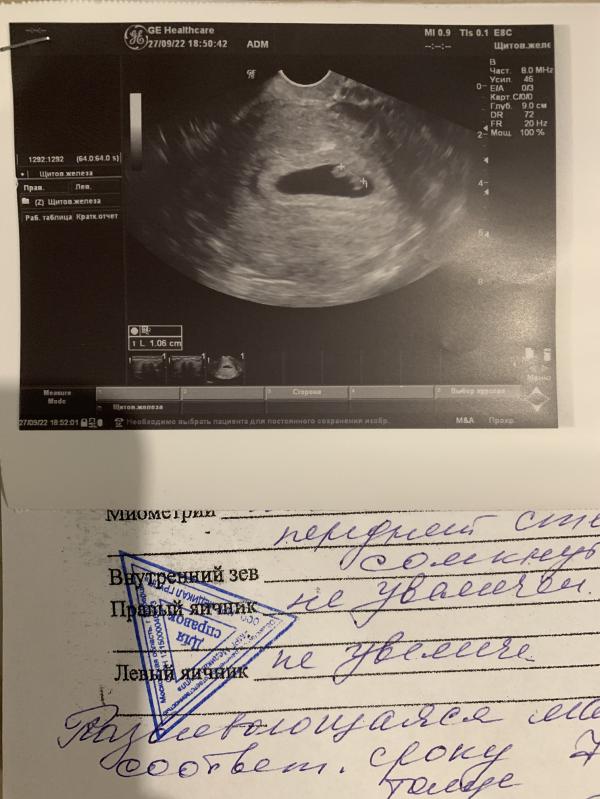

На аппарате узи видно , что это человек . ☺️☺️голова , ручки , ножки

Даже на фото это уже не точечка .

Ктр 1.06 см

ЧСС 150

Срок по кд 7 н 3 дня